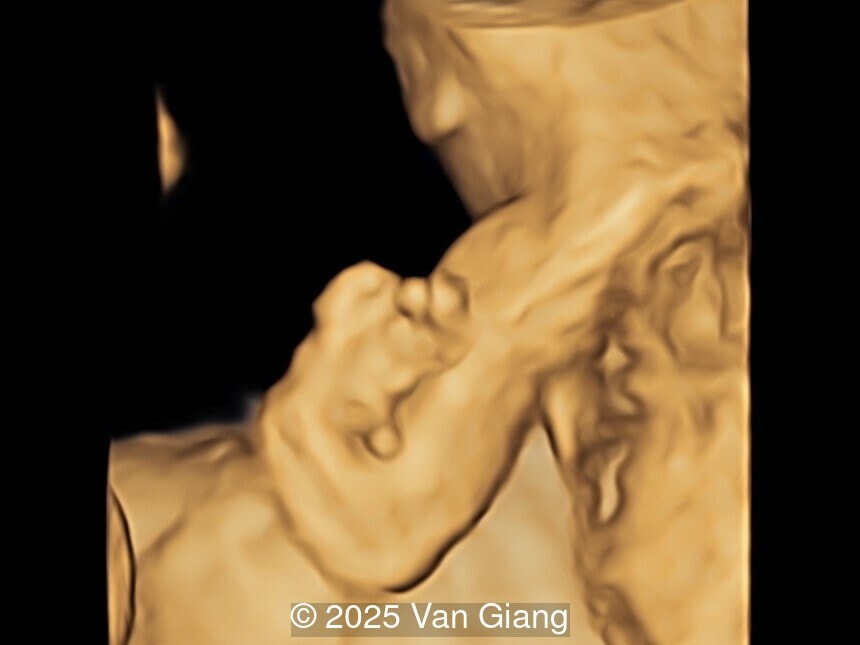

A 32-year-old primigravida presents at 20 weeks gestation without first trimester screening. Ultrasound reveals a small for gestational age fetus with the following anomalies:

Right hand

Image 3 Right hand

Ultrasound revealed severe mandibular and zygomatic hypoplasia, glossoptosis, cleft palate, and micrognathia with an abnormal facial profile. Both upper limbs showed radial ray sequence with abnormal thumbs and shortened forearms. Unilateral clubfoot was also noted. No major cardiac or visceral anomalies were observed. Based on these findings, Nager syndrome was suspected.